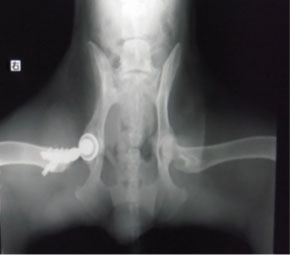

PennHIP法を実施した症例のレントゲン写真

PennHIP法(ストレスX線撮影法)

股関節の緩みを客観的に評価することが可能です。University of Pennsylvania Improvement Program (PennHIP) に評価を依頼する方法です。この機関に依頼する場合、Penn HIP により認定されている獣医師により撮影された特別な撮影像が必要となります。当院では、PennHIP 認定獣医師の資格がありますので撮影が可能です。4ヵ月齢から評価可能ですので、股関節形成不全の発症の有無を知りたい場合にも利用可能です。(PennHIP法の詳しい説明はコチラ)